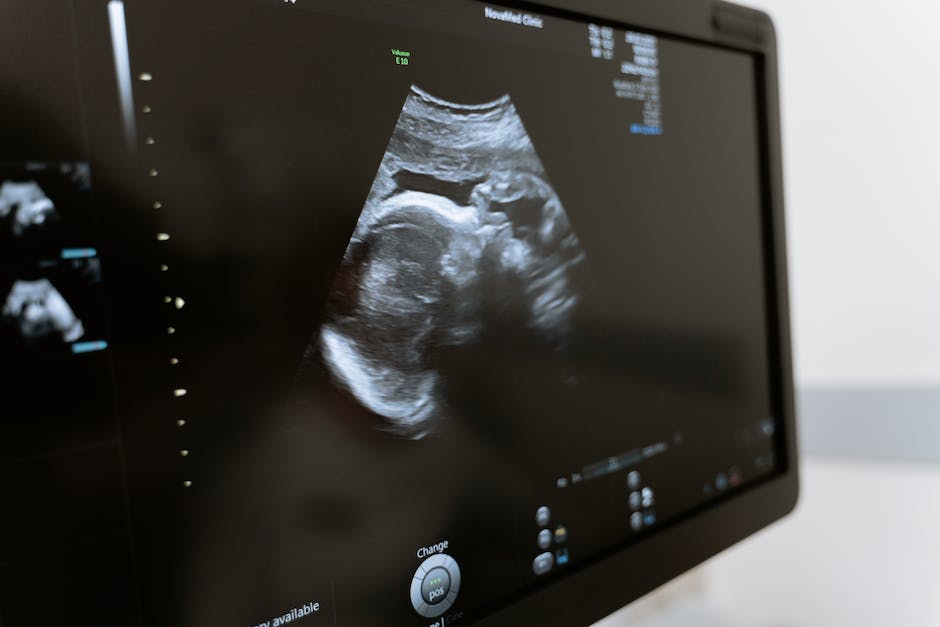

창원 산부인과에서는 고급 시설과 최신 의료 기술을 바탕으로 정확한 진단과 효과적인 치료를 제공합니다. 예를 들어, 초음파 검사를 이용하여 태아의 발달 상태를 확인하고, 자궁 내에서 질환을 조기에 발견할 수 있습니다. 또한, 현미경을 사용한 수술이 가능하며, 집중 초점 초음파 열화 소작술을 통해 자궁근종 등을 치료할 수 있습니다. 이러한 고급 시설과 최신 의료 기술을 통해 창원 산부인과는 환자들에게 정확하고 효과적인 치료를 제공하는데 주력하고 있습니다.